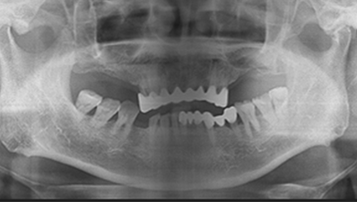

틀니 장기 사용으로 인한 골 흡수

오랫동안 틀니를 사용한 환자의 경우 턱뼈가 심각하게 얇아져 임플란트 식립을 위해 대량의 뼈이식이 필요합니다.

⚠️ 틀니 사용 10년 이상 시 50-70% 골 흡수 발생

W Dental Clinic Before & After

치료 전후사진

Before

After

뼈이식